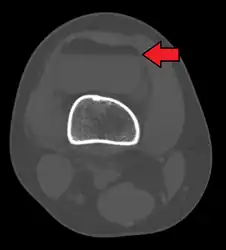

Lipohemarthrosis due to a tibial plateau fracture -

3D reconstruction of a CT image of a tibial plateau fracture -